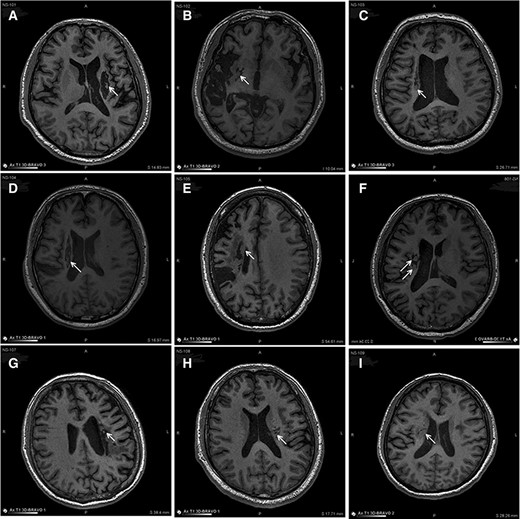

图中显示的是所有9名受试者(#101–109)在NSI-566移植后最新随访时的T1MRI图像。箭头指示梗塞腔位置。

(A):#101,24个月时,(B)#102,12个月时,(C)#103,14个月时,(D) #104,9个月时,(E)#105,14个月时,(F)#106,24个月时,(G) #107,21个月时,(H) #108,12个月时,(I) #109,14个月时。所有九个病例中梗塞腔内均有新组织生长。